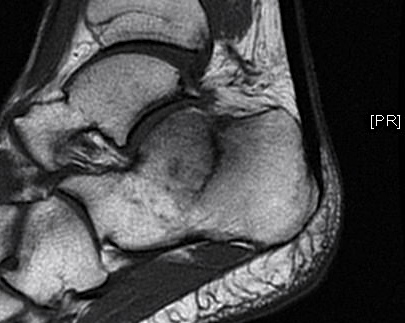

To cut then an even longer story short, I discovered afterwards, following first X-rays and then an MRI scan, that I had what in the medical field is termed bilateral calcaneus fractures. To the layman (which includes me) that means “two broken heels”. To boot I have a torn tendon just below my right ankle, and the right foot is considerably more sore than the left, as perhaps is illustrated more clearly by the pictures below, which are from the MRI scan:

In the centre of the above picture you can see a dark serrated line jutting down from the middle of my heel bone. That is a fracture. Bummer, as they say.